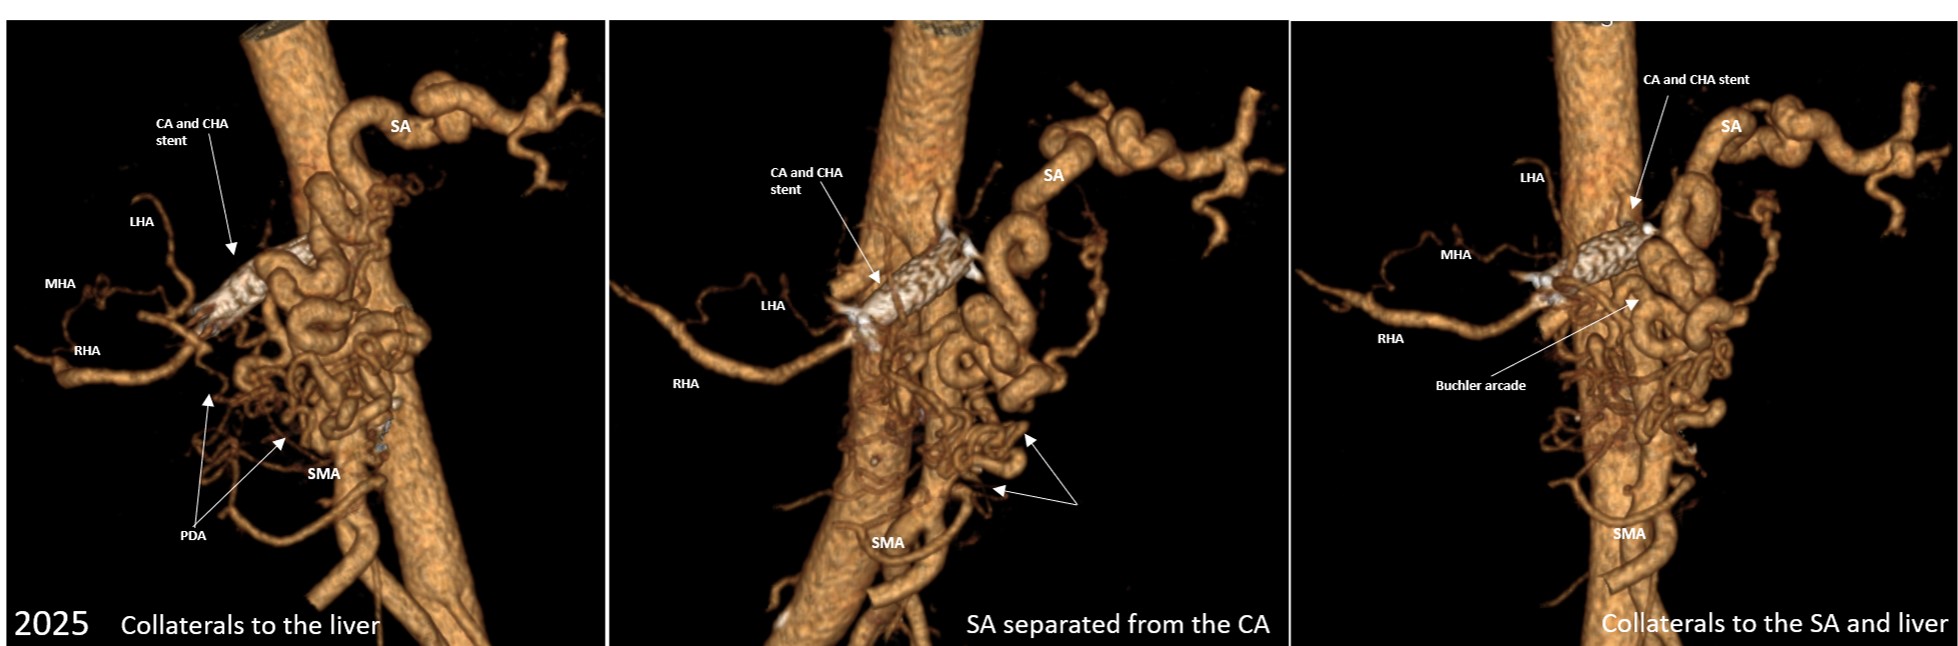

Так прошло почти девять лет, и пациент обратился с этим к нам. Кожа передней брюшной стенки на значительной площади была замещена рубцами, в центре которых находился свищ, продуцирующий до 200 мл панкреатического сока, что требовало перевязок несколько раза в день. Пациент был истощен как физически, так и морально. Обследование показало, что внутрибрюшная артериальная анатомия значимо изменена: диаметр стента в чревном стволе и общей печеночной артерии был в два раза больше диаметра этих сосудов, что говорило об отсутствии их проходимости. Левая желудочная артерия отсутствовала, как и связь селезеночной артерии с чревным стволом (ЧС). Т.е. кровотока через ЧС не было, печень, селезенка, культя желудка и ПЖ кровоснабжались коллатералями из системы верхней брыжеечной артерии (ВБА). В связи с вышеуказанными причинами, а также массивным спаечным процессом и изменением органной анатомии после более чем пятидесяти вмешательств на брюшной полости, об открытой операции не могло быть и речи, в связи с высоким риском смертельных или инвалидизирующих осложнений, которые могли возникнуть вследствие повреждения органов или нарушения их кровоснабжения. (Надо сказать, что пациенту повезло в том, что у него была редкая коллатераль между ЧС и ВБА (аркада Бюклера), и длительно существующий стеноз (сужение) чревного ствола, что привело к развитию мощных коллатералей к вышеупомянутым органам из системы ВБА до всех операций. Это помогло ему выжить после стентирования и нескольких прошиваний чревного ствола, селезеночной артерии и ветвей ВБА.)